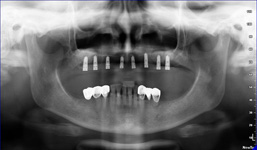

Zásadním faktorem pro úspěšné ošetření je přesná a detailní diagnostika a dokonalé naplánování celého ošetření. K tomu vždy využíváme kombinaci zjištění z klinických vyšetření a rentgenologických dat, které následně zpracováváme v plánovacím softwaru.

Jak pro ošetření stomatochirurgická tak implantologická spolu různými dostavbami kosti je vždy nutné předem znát umístění důležitých anatomických struktur (cévy, nervy, čelistní dutiny). Naše pracoviště jako první v České republice začalo

od roku 2004 používat speciální digitální zubní tomograf 3D DVT NewTom a dále také využíváme nejnovější hybridní CBCT (3D) + 2D přístroj NewTom GiANO, které umožňují 100% diagnostiku množství a kvality kosti a veškerých důležitých anatomických struktur.

Pomocí tohoto přístroje je možné zjisti skutečnou situaci v čelistních kostech pacienta tedy množství kosti - můžeme změřit skutečnou šířku i výšku kosti, i kvalitu kosti (hustotu) v místě uvažované implantace. 3D (tříprostorové) zobrazení umožňuje

zvýšit prostorovou představu operatéra ještě před vlastní operací a zároveň pacientovi lépe objasnit a ukázat oblast plánovaného zavedení implantátu.